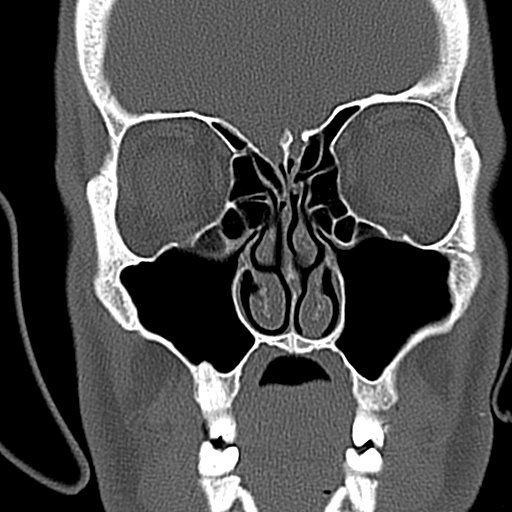

Dr. Noam Cohen is surgeon at the hiladelphia VA hospital, specializing in procedures to reduce sinus infections. For every group of people that had successful surgeries, a handful would continue to contract sinus infections. Dr. Cohen wondered, did taste have anything to do with it?

So Dr. Cohen, along with a research team from the University of Pennsylvania and the Monell Chemical Senses Center in Philadelphia studied his patients’ taste receptor tissue located in the nose (we don’t just taste with our tongues). They introduced a chemical made by the bacteria Pseudomonas aeruginosa, which it uses to communicate with other bacterium cells, to the tissue. And tissue belonging to supertasters did something unique.

The chemical is naturally bitter, so the supertasters’ receptor tissue was immediately on guard. The receptors activated tiny cilia cells, which work like moving bristles to actively sweep out the bacteria. They also signaled for more nitric oxide production, a chemical that kills bacteria.